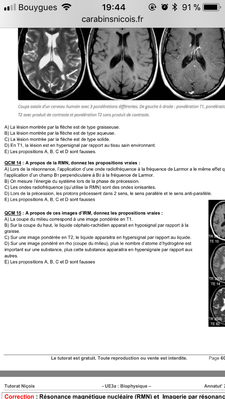

Qcms 10 item A je comprend pas pk la A est fausse Avec t1 la graisse aparait normlement en hypersignal. Et du coup il en vient de dire que la B devrait etre fausse. Pr l’item C la graisse en T2 devrait etre en hyposignal donc pk cette item est faux ( je me base sur le scheama donner sur la roneo peut etre mon resonement est totalement faux )

Ensuite pour le qcms 11 on est d’acord que si TR est court forcement c’est T1 quelque sois le TE donc on aurait pu choisir A et B

Maintenant pour le qcms 13 le fleche montre une lesion en hypersignal et c’est dit que c’est une image est ponderer en T1 donc la lesion est forcement graisseuse du coup je comprend pas pk A et D sont fause

Et enfin.qcm 15 Pour l’item B c’est faux mais sur l’image c’est ecrti TR grand et TE court donc —> rho hors en rho on sais que l’eau apparait en hypersignal or dans l’item c’est dit « hyposignal » ..